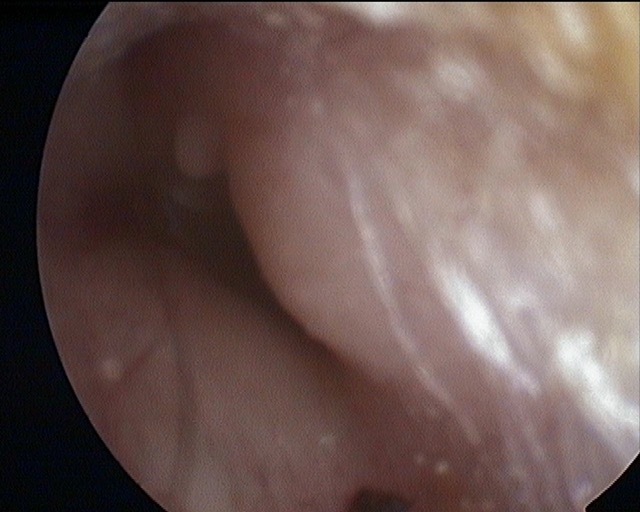

Atelectasis/Retraction

Perforation

Tympanic Membrane